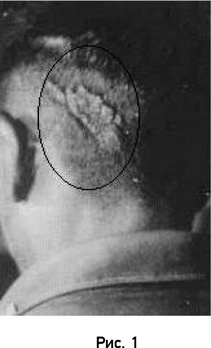

Результаты. Корреляции между ранами и родимыми пятнами Соответствие между родимым пятном и раной оценивалось как удовлетворительное, если родимое пятно и рана у ребенка и погибшего человека были в пределах области 10 см2 в том же самом анатомическом местоположении; фактически, многие из родимых пятен и ран были намного ближе к тому же самому местоположению. Медицинский документ, обычно посмертное заключение, был получен в 49 случаях. Соответствие между ранами и родимыми пятнами было оценено как удовлетворительное или лучше (по вышеуказанному критерию) в 88 % (43) всех случаев и неудовлетворительное – в шести случаях. Подробное обсуждение этих отрицательных результатов дается в моей книге «Где биология и реинкарнация пересекаются» [7]. Высокий процент (88 %) соответствия между ранами и родимыми пятнами в медицински подтвержденных случаях, повышает достоверность рассказов свидетелей, описывающих раны у погибшего человека. С другой стороны, удалось выявить четыре или пять случаев ошибочных воспоминаний свидетелей благодаря наличию заверенного медицинского документа. Большой бородавчатый эпидермальный невус на голове таитянского юноши, который, будучи ребенком, имел воспоминания о жизни своего дяди по отцу, убитого ударом в голову тяжелым ножом. ![]() Фактор случайного совпадения родимых пятен и ран значительно уменьшается, когда ребенок имеет два или больше родимых пятна, соответствующих ранам на теле погибшего человека, о жизни которого он помнит. Показанное на рисунке 1 необычное изменение кожного покрова в затылочной части головы таитянского юноши соответствует его описанию смерти дяди, наступившей почти мгновенно от удара ножа. Мальчик также имел врожденную деформацию ногтя на большом пальце ноги, что соответствует наличию у дяди хронического воспалительного процесса инфекционного происхождения на том же пальце ноги, которым он страдал в течение нескольких лет до смерти. Случаи с двумя или более родимыми пятнами Следующий ряд включает 18 случаев, в которых два родимых пятна у субъекта анатомически соответствуют точкам входа и выхода сквозных огнестрельных ранений у предшествующей личности. В 14 из них одно родимое пятно было больше чем другое, и в 9 из этих 14 документальные свидетельства показали, что меньшее родимое пятно (обычно круглое) соответствует входной ране, а большее (обычно неправильной формы) – выходной. Эти наблюдения согласуются с данными исследований морфологии пулевых ранений (входное отверстие всегда меньше, чем выходное) (Fatteh, 1976; Gordon и Shapiro, 1982). ![]() На рисунке 2 изображено маленькое круглое родимое пятно на затылке тайского мальчика, а на рисунке 3 родимое пятно большего размера и неправильной формы на передней стороне его головы. Мальчик рассказывал, что он помнит жизнь человека, который был убит выстрелом в голову сзади. (Способ смерти был проверен, но никакой медицинский документ не был доступен.) В дополнение к девяти случаям я исследовал другой случай, представленный Mills, где имели место характерные топологические признаки родимых пятен, соответствующих сквозному пулевому ранению. Этот случай был подтвержден посмертным медицинским заключением (Mills, 1989). Я вычислил достоверность возникновения двух родимых пятен, корректно соответствующих двум ранениям. Площадь поверхности кожи среднего взрослого мужчины равна 1,6 м2 (Spalteholz, 1943). Эта площадь соответствует 160 квадратам размером 10×10 см. Вероятность, что одно родимое пятно на теле человека соответствовало бы местоположению раны в пределах области из 160 квадратов, составляет только 1/160. Однако вероятность совпадения двух родимых пятен с двумя ранами была бы 1/(1602), то есть 1/25600. (Этот расчет предполагает, что родимые пятна однородно распределены по всей поверхности тела. На самом деле это не совсем корректно… однако для поставленной задачи малыми вариациями можно пренебречь…) ![]() …Бирманская девочка рассказала, что она помнит жизнь ее тети, умершей в отделении хирургии врожденных пороков сердца. Этот ребенок имел длинное, вертикальное линейное гипопигментированное родимое пятно по средней линии нижнегрудинной области, которое соответствовало месту хирургического разреза у ее тети во время операции на сердце. (Мною [Я. Стивенсоном. – Прим. автора] было получено и медицинское заключение по данному случаю.) Три примера врожденных дефектов На рисунке 4 показана правая сторона головы турецкого мальчика с уменьшенным, плохо сформированным ухом (односторонняя микроотия). Он также имел недоразвитие правой стороны его лица (гемифациальная микросомия). Из его рассказов следовало, что он помнил эпизоды жизни человека, который получил огнестрельное ранение правой части лица и черепа прямой наводкой с близкого расстояния. ![]() Раненый был госпитализирован в больницу, где умер шестью днями позже от повреждений мозга, вызванного выстрелом. (Я [Я. Стивенсон. – Прим. автора] получил копию истории болезни, подтверждающую диагноз.) ![]() На рисунке 5 можно видеть врожденное почти полное отсутствие пальцев на руке (односторонняя брахидактилия) у ребенка из Индии. Ребенок описал свои воспоминания о жизни другого ребенка, который попал правой рукой в диск-измельчитель сельскохозяйственной фуражной машины и потерял пальцы. В большинстве случаев брахидактилии имеет место укорочение только средних фаланг. В данном случае кости фаланг отсутствовали вообще, а пальцы имели вид бугорков. Односторонняя брахидактилия чрезвычайно редкий врожденный порок развития, и я [Я. Стивенсон. – Прим. автора] не нашел публикаций по подобным случаям, хотя коллега (пластический хирург) показал мне фотографию одного своего пациента, пребывавшего у него на лечении. ![]() На рисунке 6 можно видеть врожденное отсутствие голени (односторонняя гемимелия) у бирманской девушки. Она сообщила об имевших место воспоминаниях из жизни другой, которая попала под поезд и погибла. Очевидцы подтвердили данный случай и рассказали, что сначала колесом отрезало правую ногу, а затем поезд переехал через туловище девушки. |